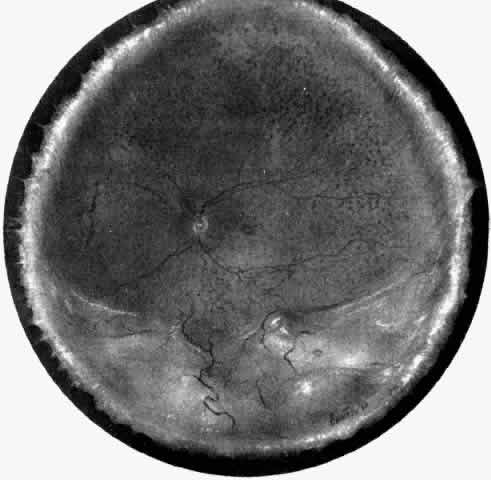

Uveal Effusion Syndrome

The pathogenesis of uveal effusion syndrome (Fig. 18), also referred to as idiopathic ciliochoroidal effusion, has not been clearly defined, but it is now thought to be primarily due to an abnormality in scleral thickness.92 It is usually unassociated with any other ocular or systemic abnormalities and occurs in the noninflamed eyes of middle-aged men as an insidious, progressive, usually bilateral non-rhegmatogenous retinal detachment with shifting fluid. This detachment can occur before there is any detectable ciliochoroidal elevation. Other findings include flat peripheral ciliochoroidal effusion, scattered retinal exudates, and localized areas of RPE hypertrophy and hyperplasia (“leopard spots”) (see Fig. 1).12,13,69,70,92,94 Evidence of uveal, retinal, or vitreous inflammation is minor or absent (see Fig. 18).

Fig. 18. A nonrhegmatogenous retinal detachment associated with a ciliochoroidal effusion in a 46-year-old man. A ciliary body biopsy, performed because a ring melanoma was suspected, showed a mild lymphocytic infiltrate. Similar changes developed in the fellow eye, and the patient was considered to have uveal effusion syndrome. Exhaustive studies gave no clues to the etiology. The cerebrospinal fluid protein was slightly elevated. During a 10-year period, the patient's vision decreased to count fingers (H & E, × 440). (Courtesy of the Armed Forces Institute of Pathology, Washington, DC)

The literature does not clearly distinguish between uveal effusion syndrome and idiopathic ciliochoroidal effusion.9,65 They may most likely represent the same entity. In fact, findings similar to those for uveal effusion syndrome have been described in eyes with idiopathic ciliochoroidal effusion (Figs. 19B and 20C and D). An idiopathic ciliochoroidal effusion, however, is considered clinically and pathogenetically different from an effusion in a nanophthalmic eye, which is small and chronically hypotonous.89

Fig. 20. A 61-year-old man presented with a 10-day history of decreasing vision in the left eye.96 Examination disclosed a vision of hand motions, an irregularly shallow anterior chamber, closure of the angle, and an intraocular pressure of 45 mmHg. The ora serrata was visible without scleral depression. Ophthalmoscopic examination disclosed two large areas of solid-appearing lesions of the pars plana and anterior choroid (situated superonasally and inferotemporally), detachment of the retina, and a diffuse pigmentary disturbance, which was linear in some areas. Transscleral transillumination disclosed that areas of solid choroidal lesions lit up when viewed through the pupil. Radioactive phosphorus uptake was 16% at 1 hour, 18% at 24 hours, and 44% at 72 hours. The eye was enucleated because of the suspicion of a malignant melanoma. A. An extensive ciliochoroidal effusion (asterisks) showing mild diffuse and marked focal (arrowhead) infiltration of lymphocytes. The equatorial sclera is markedly thickened, and there is a large serous detachment of the retina (H & E, × 17). B. Edematous choroid with a large aggregate of lymphocytes (H & E, × 100). C. The equatorial area shows a thickened sclera, an edematous choroid with diffuse and marked focal aggregates of lymphocytes, localized area of retinal pigment epithelial hypertrophy and hyperplasia (arrowheads), slight folds in the retinal pigment epithelium and inner aspect of the choroid (arrows), and proteinaceous material (asterisk) in the subretinal space (H & E, × 40). D. A choroidal effusion with overlying proliferation of retinal pigment epithelium in nodular and linear configurations. Proteinaceous material is present in some areas in or beneath the retinal pigment epithelium (arrowheads) (H & E, × 180).

Histopathologically, there is a variable lymphocytic infiltrate in the ciliary body and choroid (see Figs. 19 and 20; Fig. 21).96